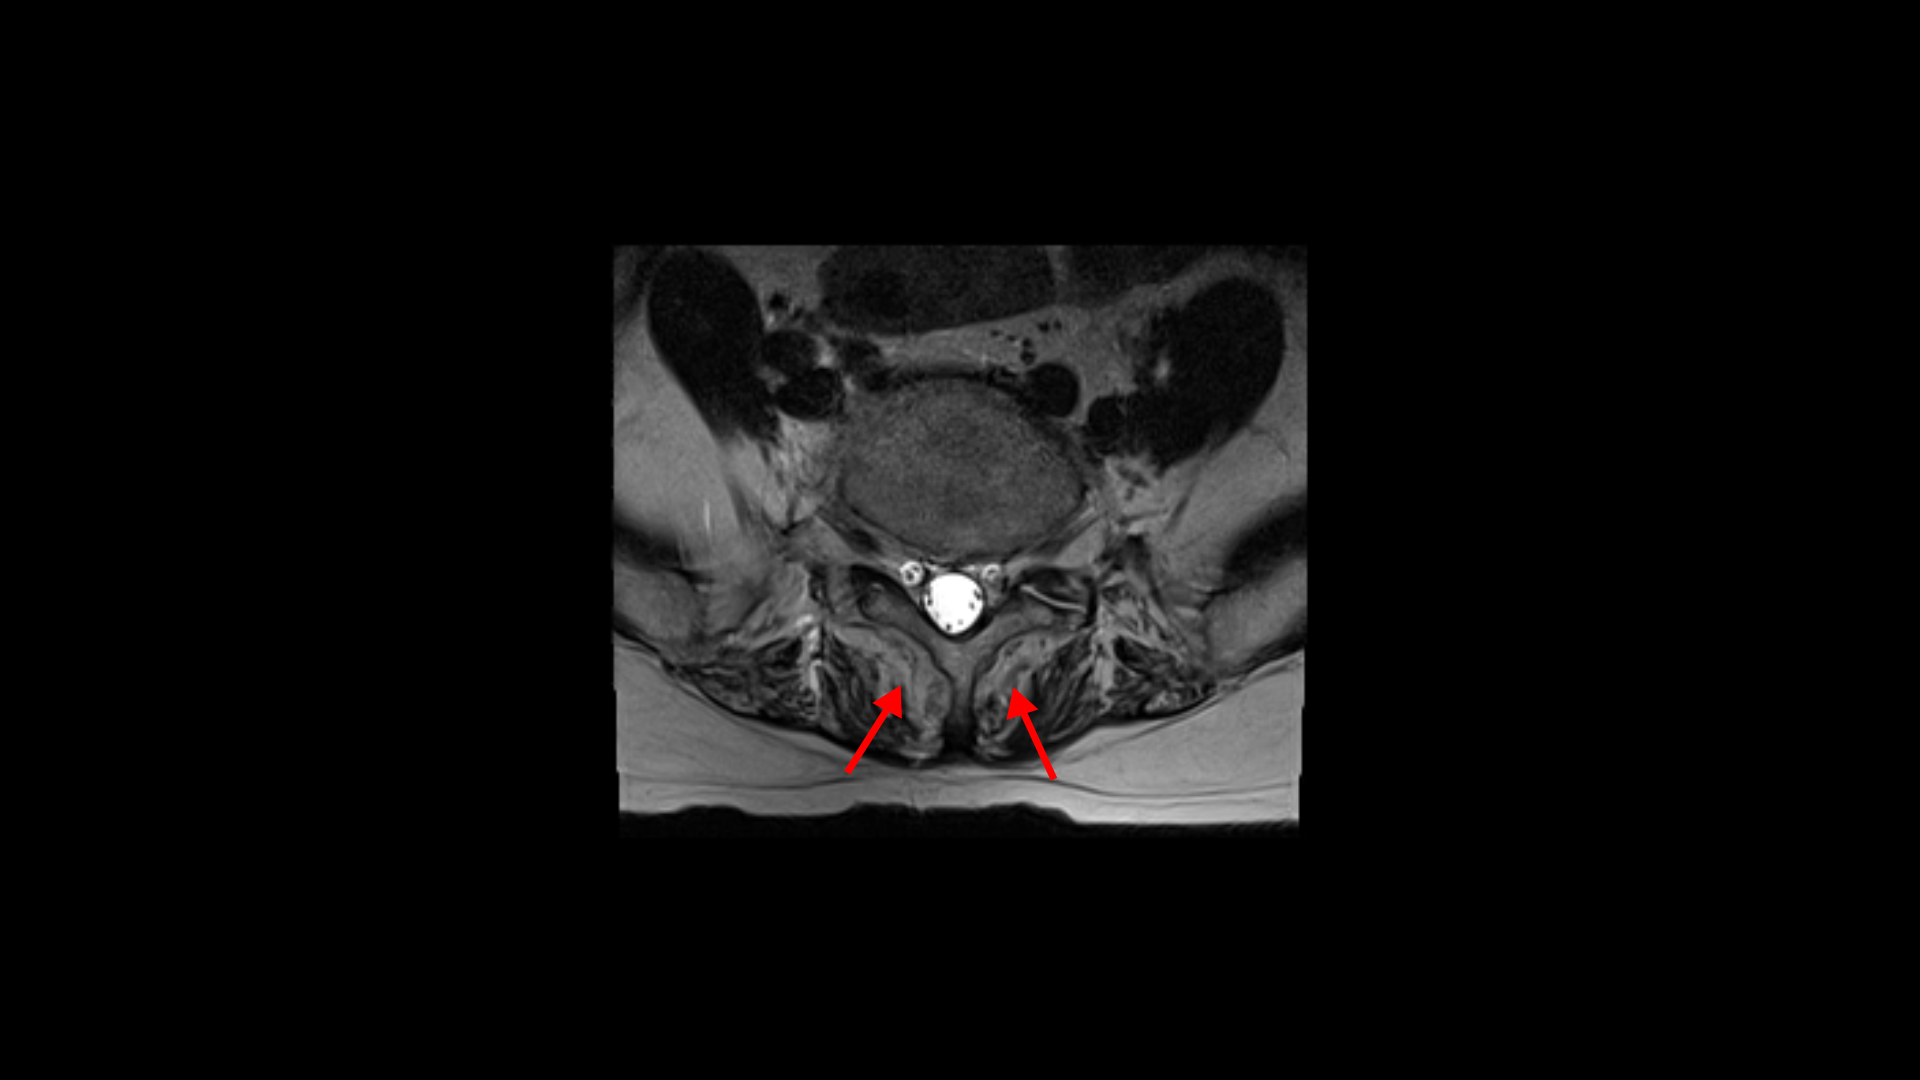

이분 MRI를 보면 74세의 연세답게 여러 마디의 퇴행성 디스크가 있습니다. 하지만 심하지 않습니다.

3번 4번에 황색 인대가 조금 두꺼워진 중심성 협착이 보이지만 역시 심하지는 않습니다.

좌우의 신경구멍도 막힌 곳이 없습니다.

이 환자분의 일어서면 허리가 구부러지고 다리가 아파 걷기 어려운 이유는 근감소증 때문입니다. 특히 근육 중에서도 MRI에서 보면 허리 뒷부분에서 허리를 펴주는 근육인 기립근이 보시다시피 하얗게 지방으로 변해있습니다.

이분하고 증상이 비슷한 다른 근감소증 환자분의 기립근도 마찬가지입니다.